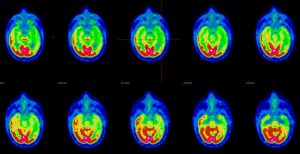

Suspicion d’aphasie primaire progressive TEP-FDG

Femme de 70 ans, suspicion d’aphasie primaire progressive

Hypométabolisme temporo-pariétal et frontal gauche

Aphasie Primaire Progressive (APP)